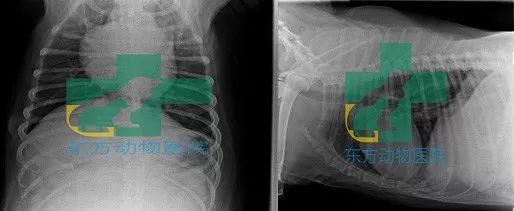

阴道分泌物涂片染色、x光片、B超、cbc、c反,生化12项

4、诊断:初步诊断开放性子宫蓄脓